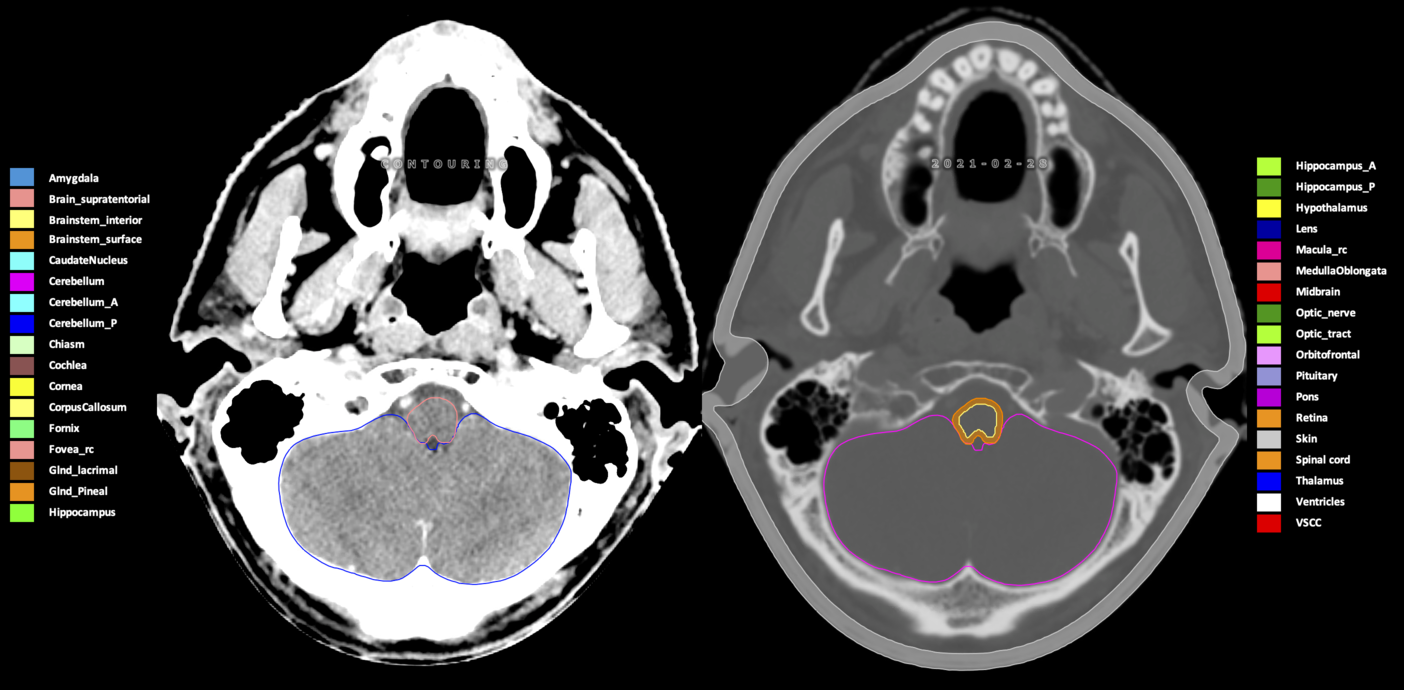

Included are all OARs known to be relevant for radiation-induced toxicity in neuro-oncology: brain, brainstem (midbrain, pons, medulla oblongata), chiasm, cerebellum (anterior & posterior), cochlea, cornea, hippocampus (anterior & posterior), hypothalamus, lens, lacrimal gland, optic nerve, pituitary, skin, and vestibular & semicircular canals. To further facilitate research on cognition, vision and radiological changes after irradiation of the brain, potential clinically-relevant OARs are included: amygdala, caudate nucleus, cerebellum (anterior & posterior), corpus callosum, fornix, macula, optic tract, orbitofrontal cortex, periventricular space (PVS), pineal gland, and thalamus.

Three-dimensional delineation of the 25 consensus OARs for neuro-oncology are shown on CT (WW/WL 120/40, 3000/600), 3T MR images, (T1Gd, T2FLAIR 1mm) and 7T MR (MP2RAGE 0.7 mm). All are presented in transversal, sagittal and coronal view.